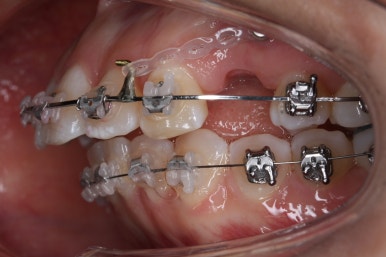

윗니는 발치를 했고, 잇몸뼈에 미니스크류를 식립하여 앞니를 뒤로 당겨넣고 있습니다.

이 뽑은 자리가 점점 줄어드는 것이 보입니다.

아랫니도 많이 가지런해졌네요.

이 뽑은 자리가 반 이상 줄어든 것 같네요. 아랫니는 마무리를 해도 될 정도로 많이 좋아졌습니다.

이 쯤되면 중간평가를 하게 됩니다.

입 모양을 보고 얼마나 더 넣을지, 앞으로는 어떤 방향으로 치료하게 될 지 다시 한 번 점검하는 것이지요.

이 뽑은 틈은 거의 없어져가고 있고, 중간평가 이 후 더 필요한 위치에 미니스크류를 추가하여 당기고 밀고 밀어넣고 다양한 작업을 해주게 됩니다.